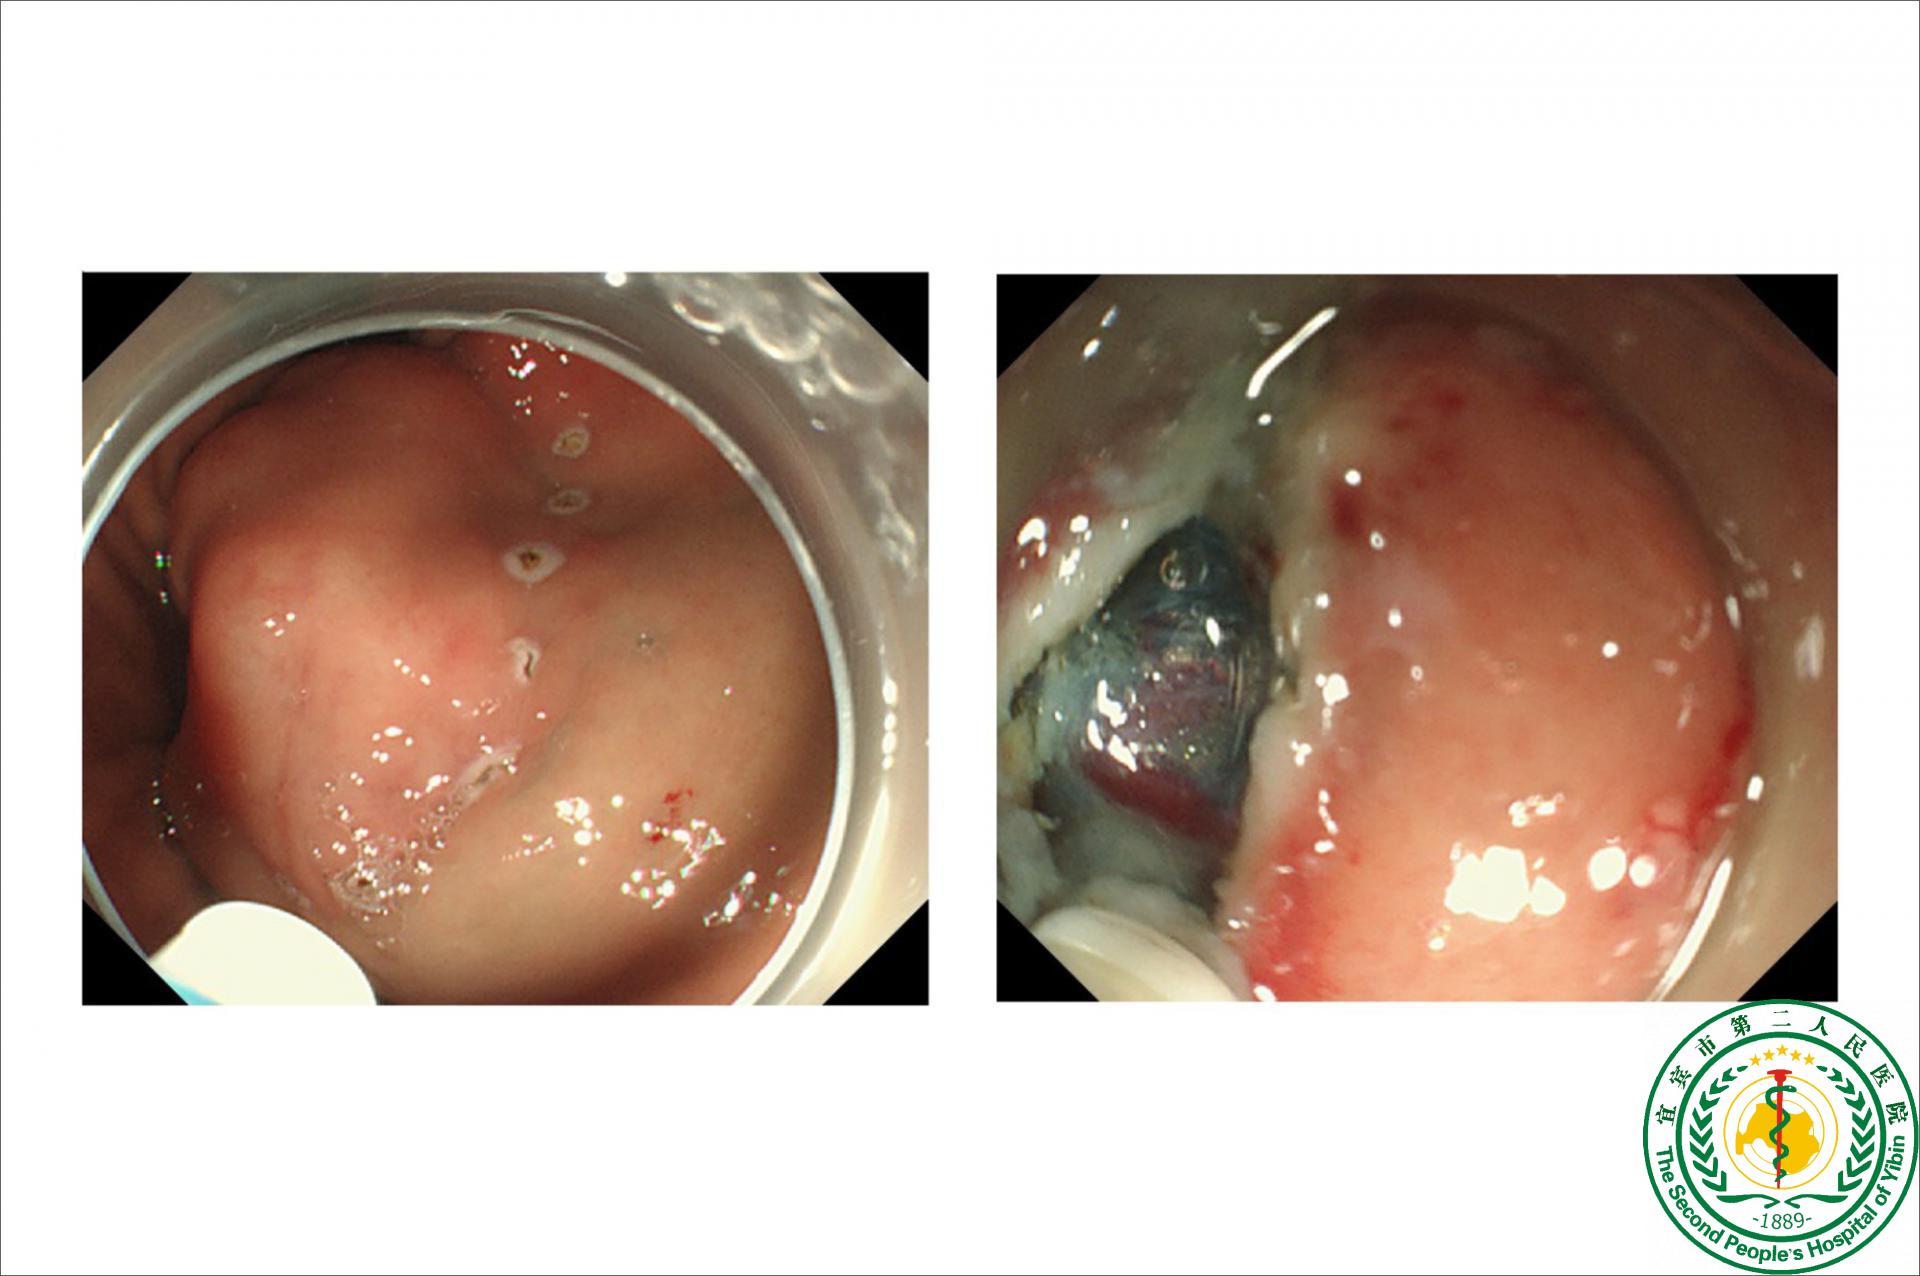

胃肠外科成功为一名间质瘤患者极限保胃

胃肠外科成功为一名间质瘤患者极限保胃19517